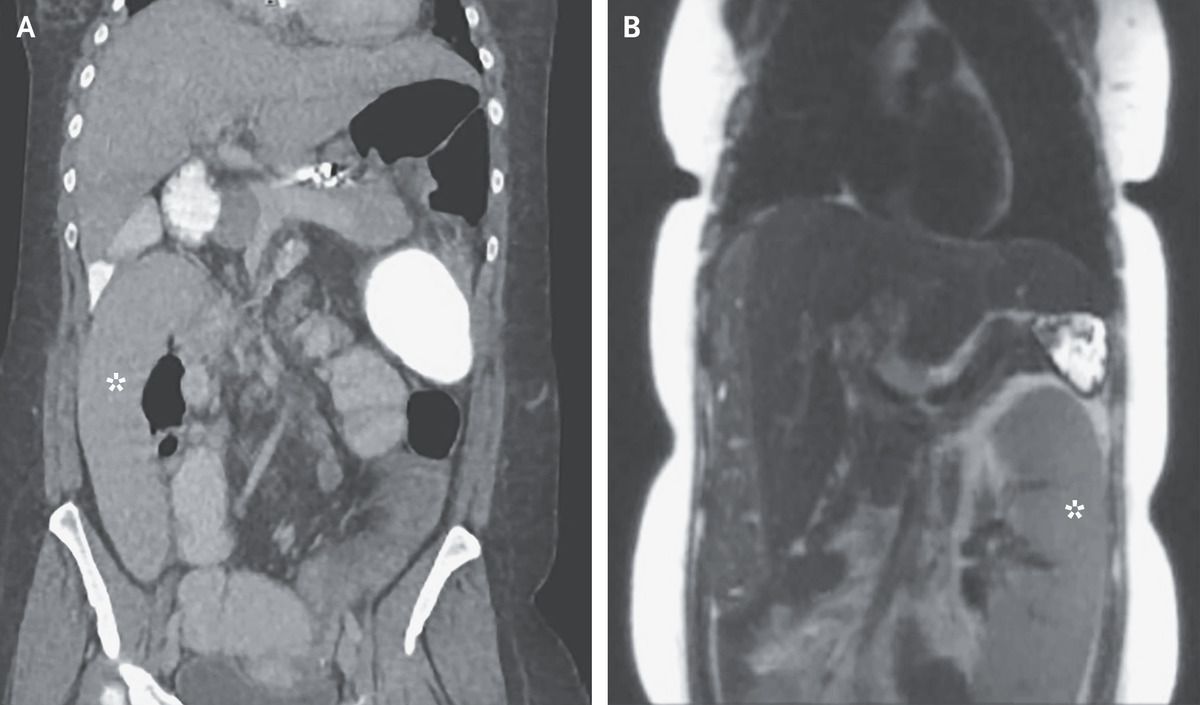

A 36-year-old woman presented to the emergency department with a 1-day history of abdominal pain and vomiting. She had ulcerative colitis, as well as cirrhosis due to primary sclerosing cholangitis, and her surgical history included a total colectomy, cholecystectomy, and appendectomy. The physical examination was notable for diffuse abdominal tenderness. Laboratory studies showed a lipase level of 682 IU per liter (reference range, 5 to 50). Abdominal computed tomography showed that the spleen was located in the right lower quadrant (Panel A, asterisk), with the pancreatic tail looped inferiorly and to the right. Two days before the current presentation, the patient had undergone routine screening for hepatocellular carcinoma by means of magnetic resonance cholangiopancreatography, which had shown the spleen located on the left side of the abdomen (Panel B, asterisk), along with a normal-appearing pancreas. No biliary stones were seen. Wandering spleen is an uncommon condition that can occur as a result of laxity of the splenic ligaments. As the spleen moves, it can cause torsion of the structures in or near the splenic hilum, including the pancreatic tail, which may cause acute pancreatitis. Definitive treatment for this condition is splenectomy. The patient received parenteral pain-control treatment and hydration, and her abdominal pain and vomiting resolved. In this case, splenectomy was deferred because evaluation for liver transplantation was ongoing.